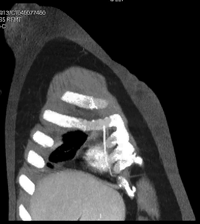

UAB has long been a leader in cardiovascular disease, and cardiac imaging. We have an excellent program of adult and pediatric heart disease, including a world class cardiac surgery program, cardiac transplantation, pulmonary hypertension, heart failure, etc. In cardiopulmonary imaging, the fellow will receive training in (a) interpretation of all aspects of thoracic imaging including conventional radiographs of the chest, chest CT, cardiac CT, and MRI; (b) percutaneous biopsy and drainage procedures in the thorax; (c) exposure to CT/PET; (d) cardiopulmonary pathology and brief rotation on clinical services; (e) research activities.

Extensive clinical material is available in both cardiac and pulmonary diseases, including 4000 cardiac catheterizations in adults, 800 pediatric cardiac catheterizations, more than 20,000 chest CT's and 100,000 chest radiographs, and about 600 cardiac MR examinations annually. There is excellent interaction between the Radiology Department, and the Divisions of Adult and Pediatric Cardiology, Pulmonary Medicine and Cardiothoracic Surgery.